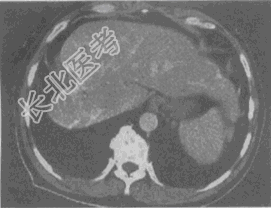

- 单项选择题女,56岁, 腹胀、双下肢水肿、乏力、食欲缺乏,影像所见如下图, 最可能的诊断是

A、酒精性肝硬化并肝血管瘤

B、血吸虫肝硬化并肝癌

C、肝炎后肝硬化并肝癌

D、局限性脂肪肝

E、原发性肝癌